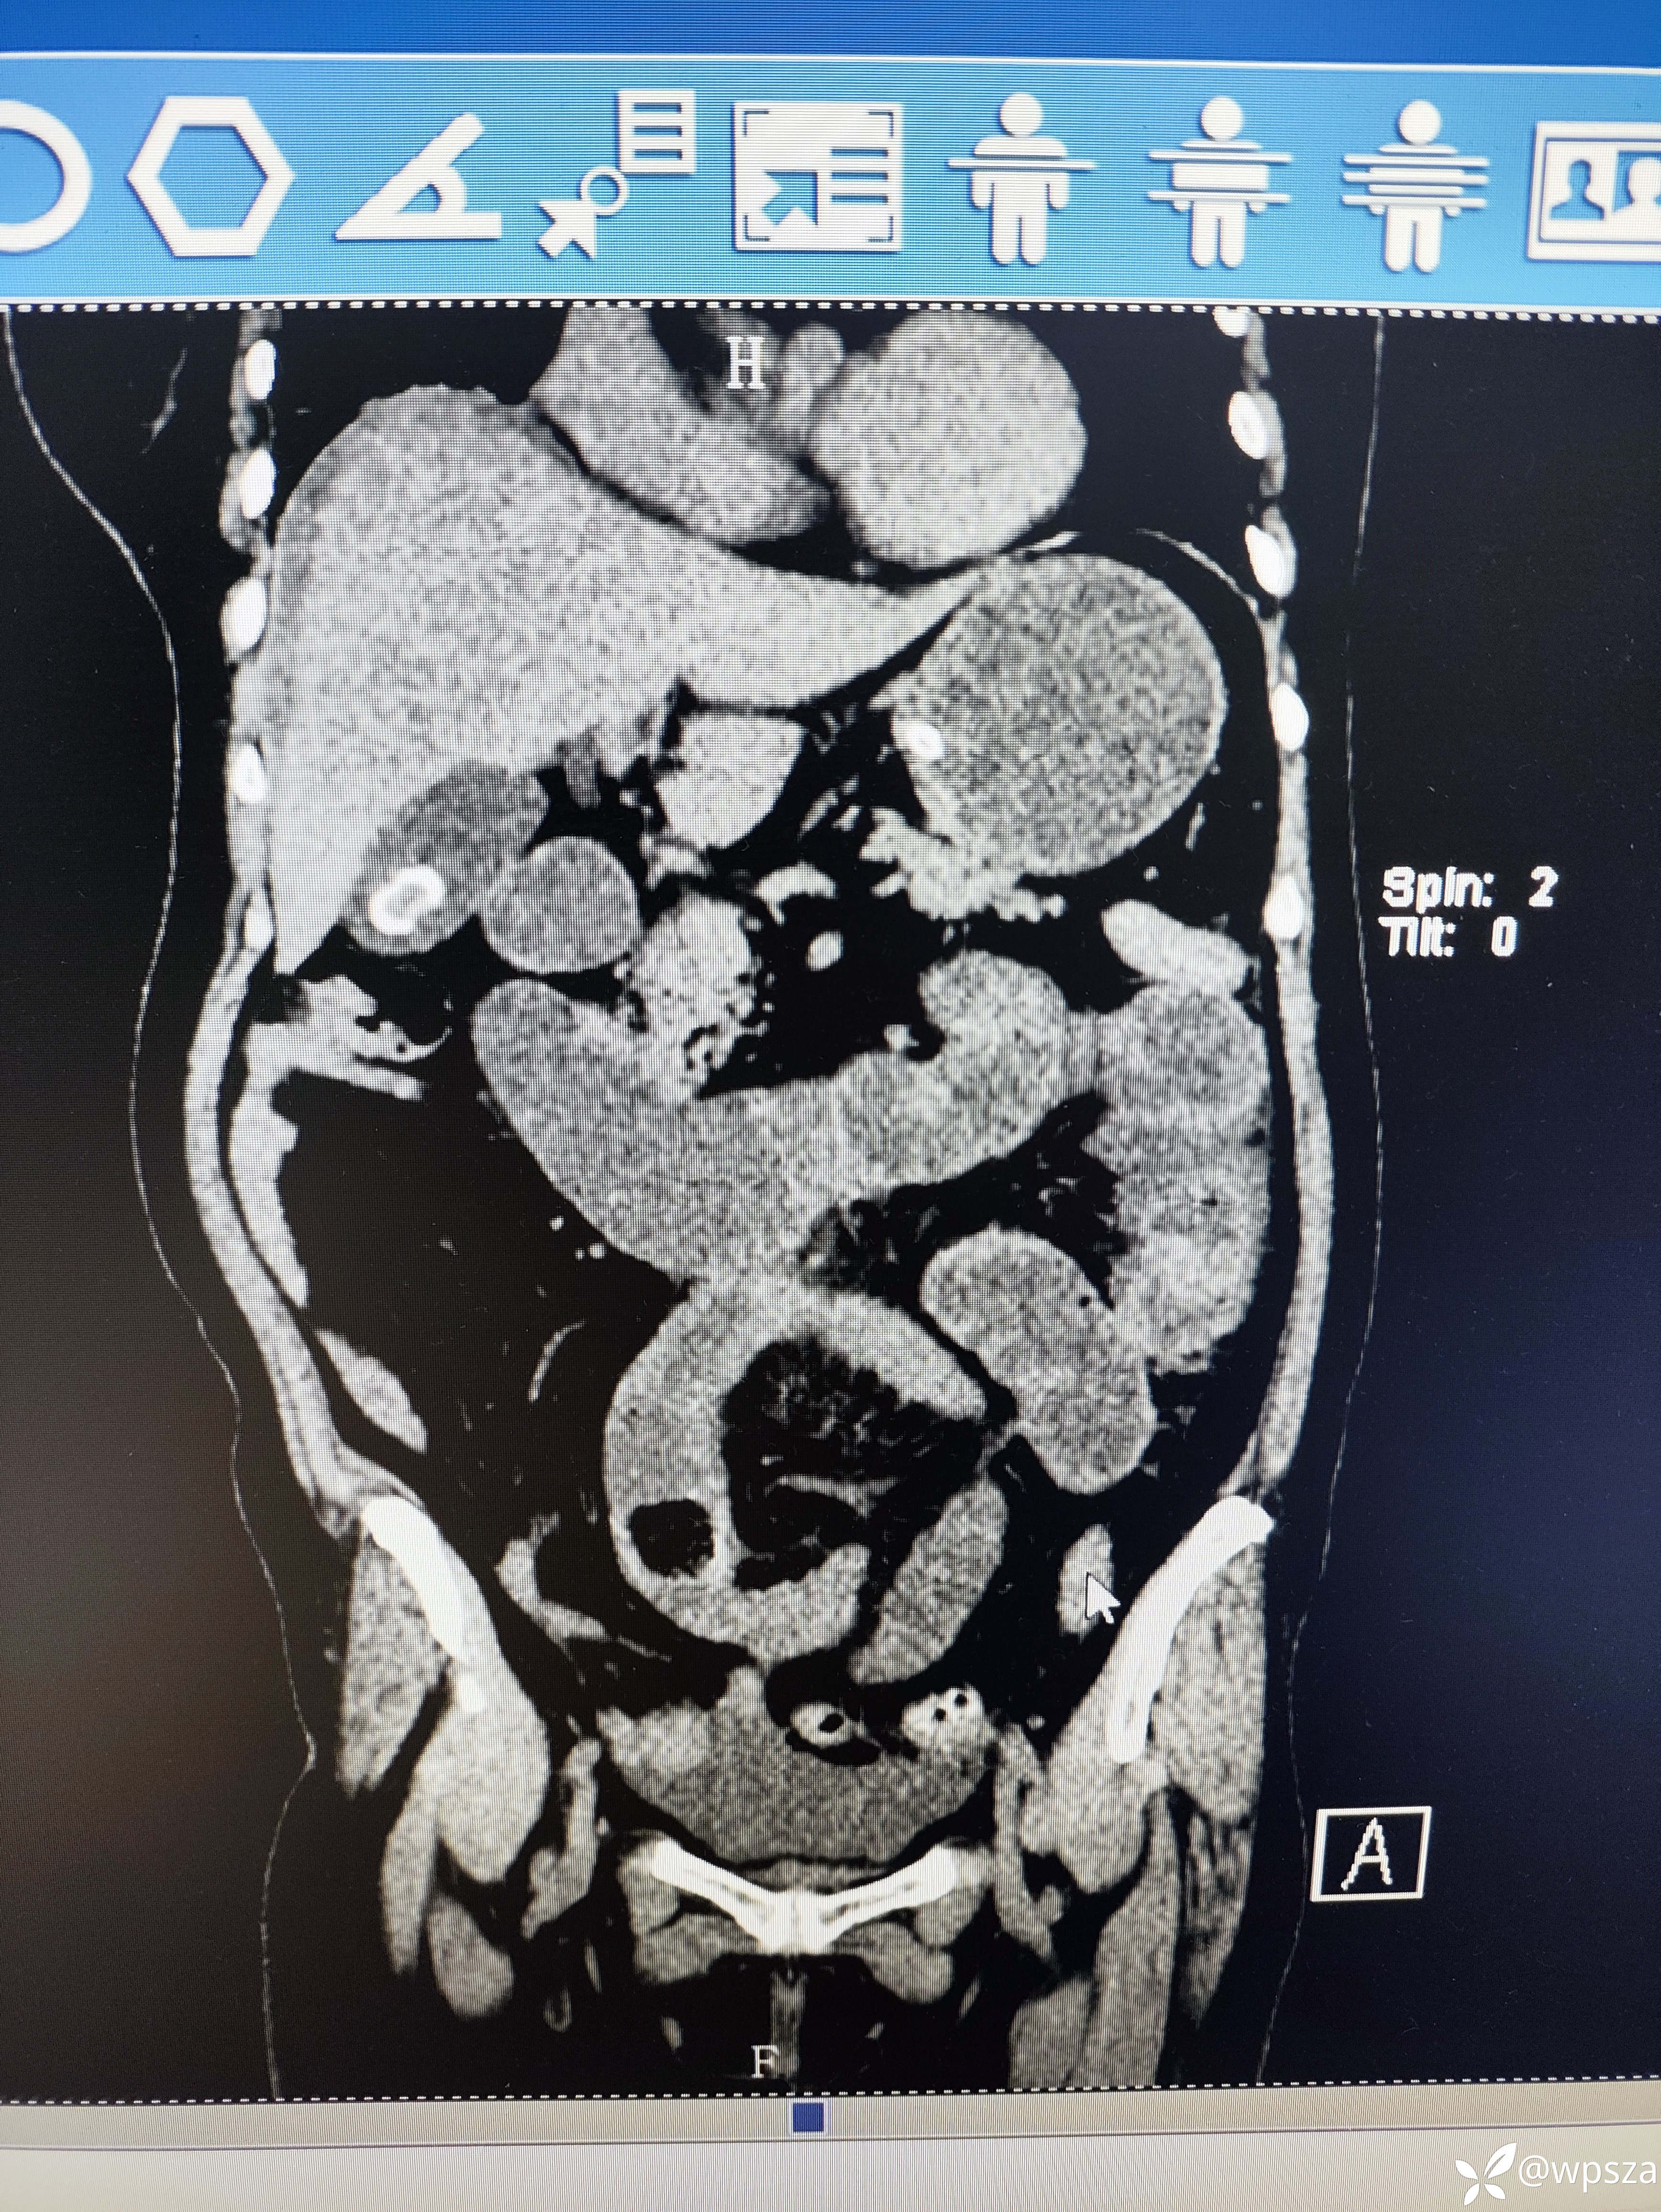

【患者信息】:女,70岁

【主诉】:腹痛1月余,加重一周

【检查】:腹部CT

【临床诊断】:肠梗阻

【治疗经过及结果】:保守治疗无效,切开取石

溶石后柿石从胃进入肠道引起肠梗阻